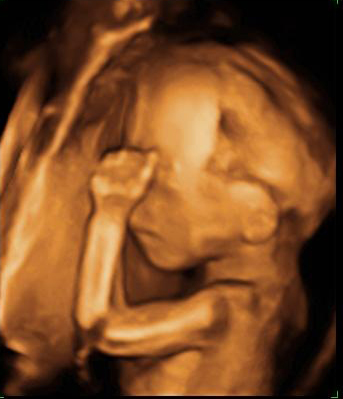

Ecografía Embarazo 2D y 3D Semana 20 - MALFORMACIONES FETALES

Ecografía Embarazo 4D Semana 20 - MALFORMACIONES FETALES